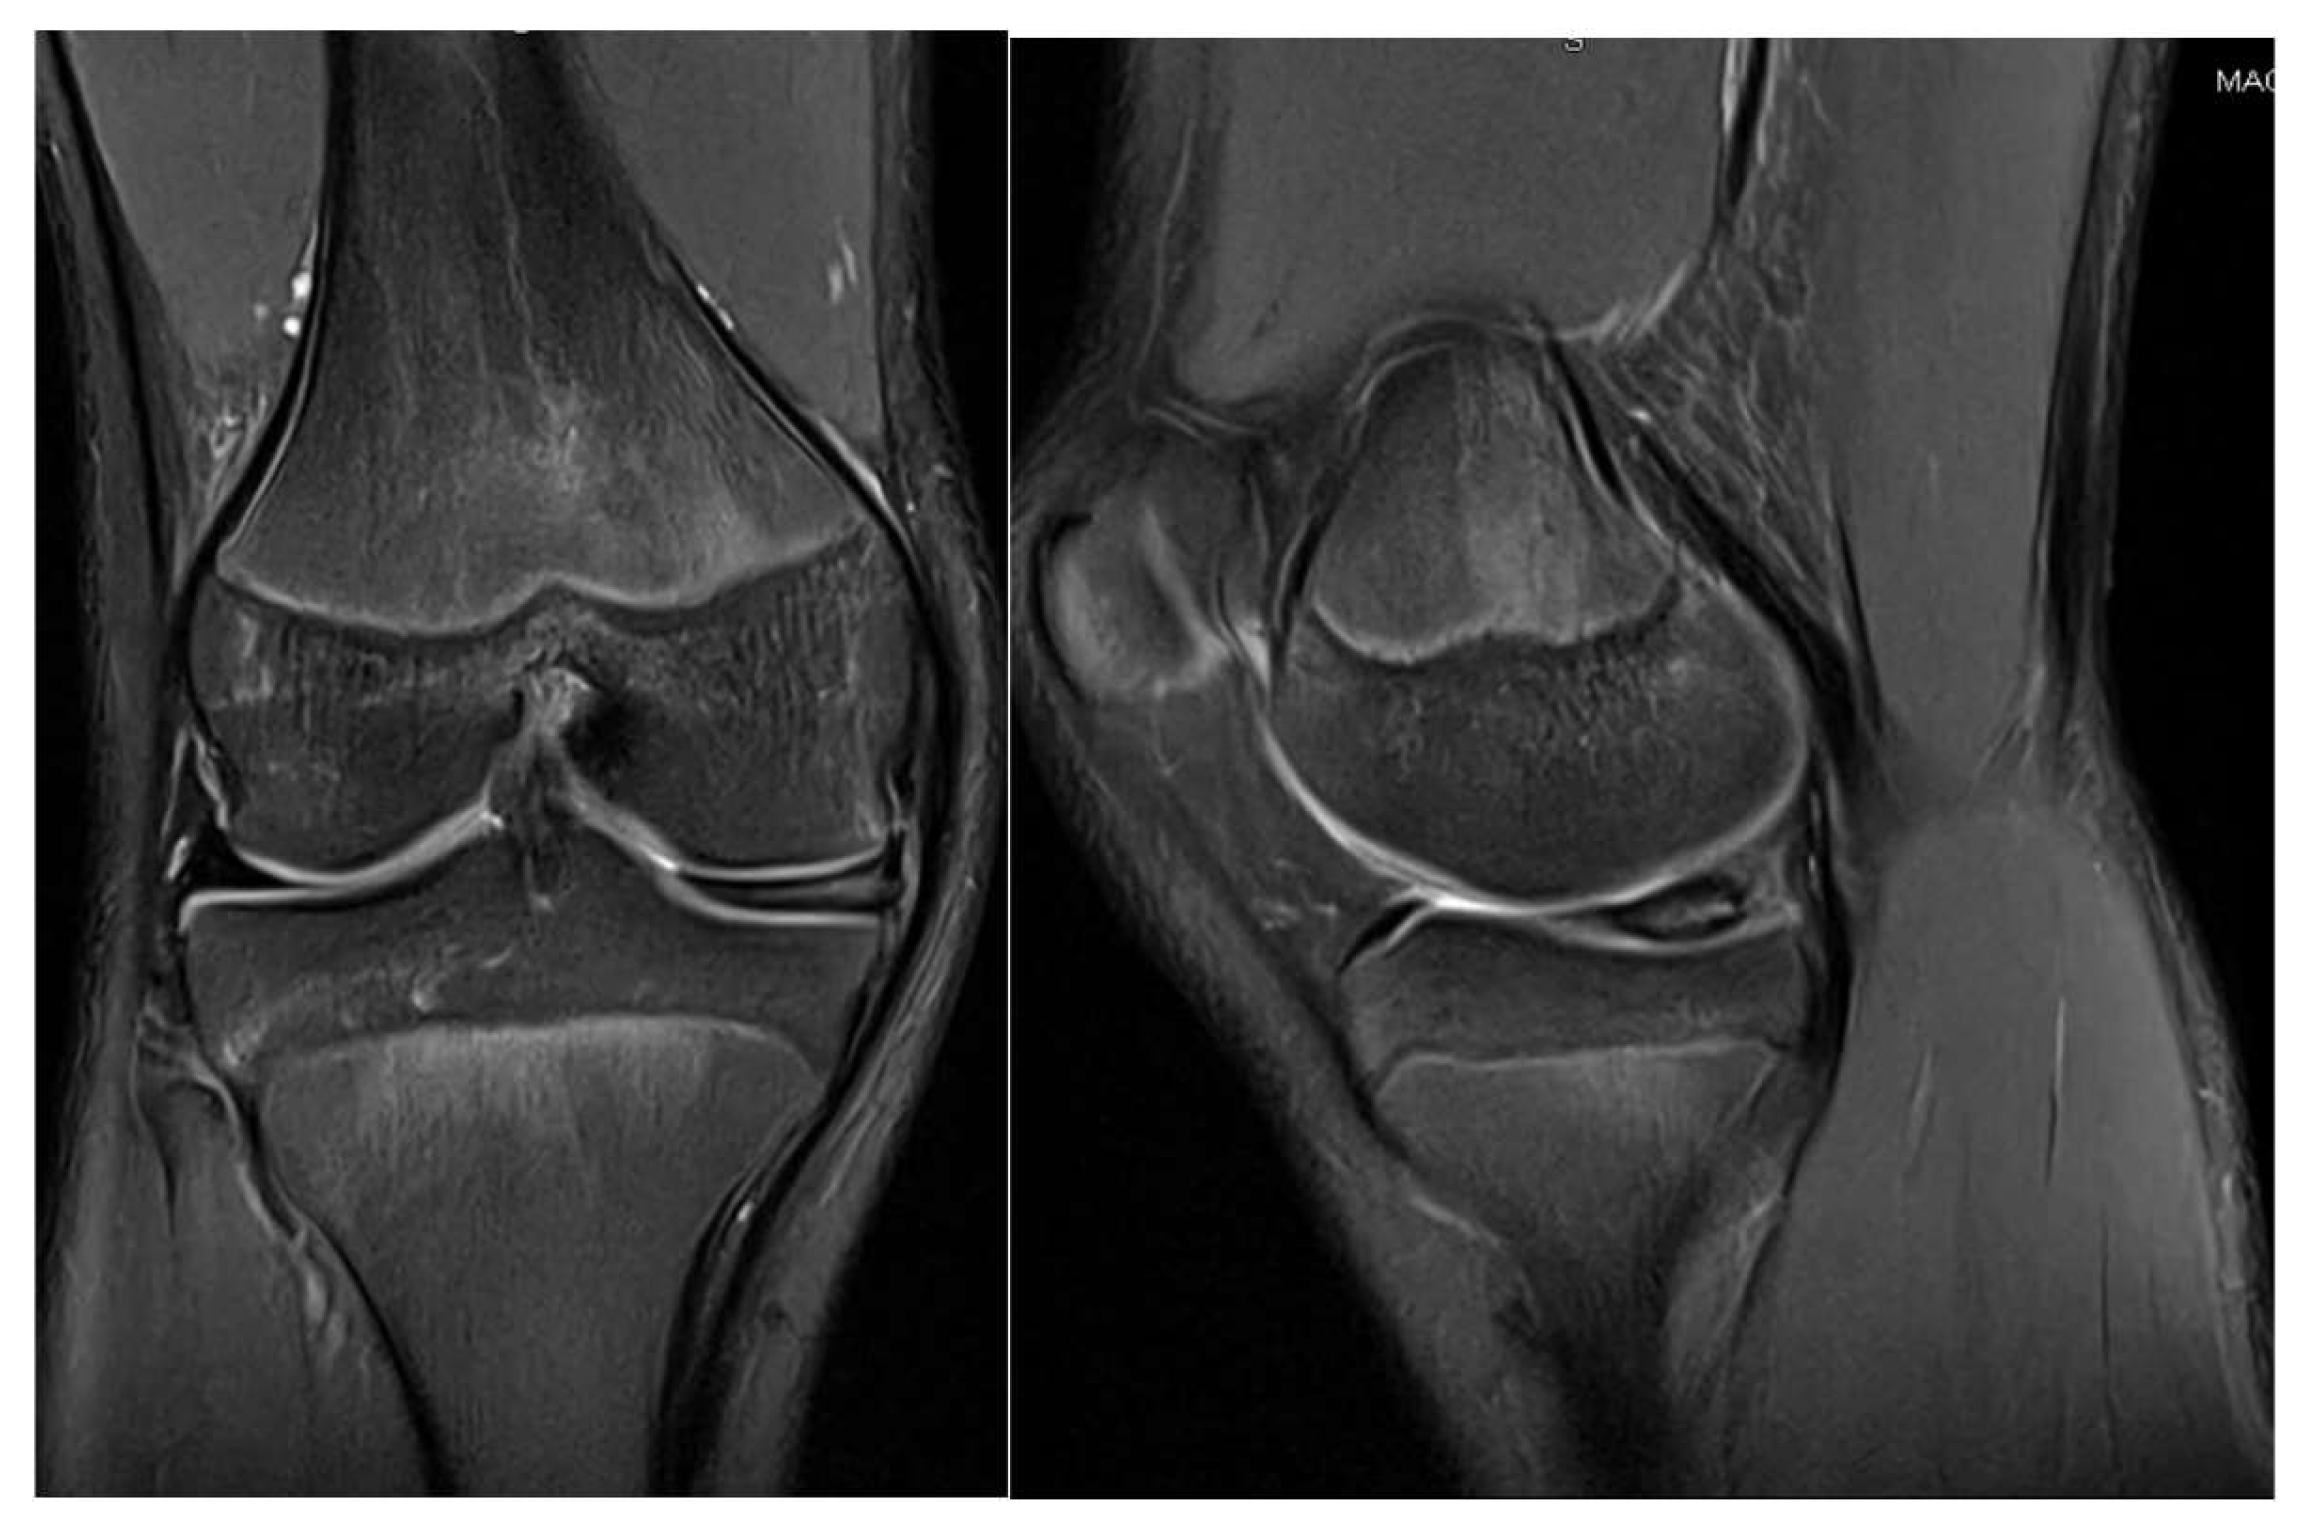

3.1. Case 1—P.E.

3.2. Case 2—S.C.S.

3.3. Case 3—G.L.

| P.E. | 12 | Bilateral (symptomatic right) | Chronic pain, effusion, normal ROM | None | 3 surgeries: partial meniscectomy (12 years), suture for horizontal tear (13 years), suture for radial tear (14 years) | 1 year after third surgery: symptom-free, resumed school sports |

| S.C.S. | 13 | Left | Pain, occasional locking, normal ROM | Dancing | 1 surgery: partial meniscectomy and suture for horizontal tear (13) | 6 months: symptom-free, full ROM, resumed dancing |

| G.L. | 14 | Bilateral (symptomatic right) | Pain, medial tenderness, normal ROM | Basketball | 1 surgery: partial meniscectomy and suture for horizontal tear (14) | 6 months: symptom-free, full ROM |